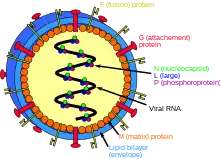

| Nipah virus infection | |

| Structure of a Henipavirus | |

The Nipah virus (NiV) is a type of RNA virus in the genus Henipavirus, which normally circulates among fruit bats of the genus Pteropus.[7] Spread typically requires direct contact with an infected source; it can both spread between people and from other animals to people. Diagnosis is based on symptoms and confirmed by laboratory testing.[2][1]